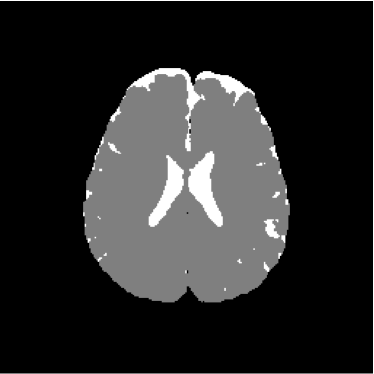

Refer to caption

Figure 14: Ground truth image (13th slice) generated by polynomial net classification

Figure 13 shows the training set mounted on the 13th slice of the volume of ADC maps. Figures 14 and 15 show the ground truth volume and the 13th slice, respectively.